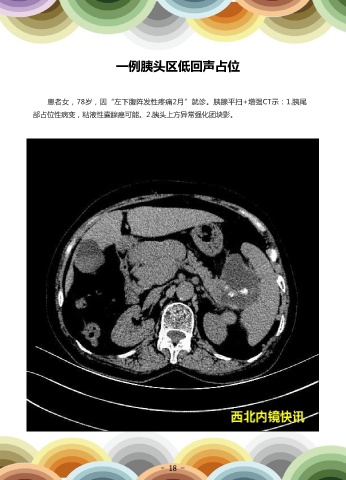

一例胰头区低回声占位

患者女,78岁,因“左下腹阵发性疼痛2月”就诊。胰腺平扫+增强CT示:1.胰尾                                        超声内镜检查:胰头区低回声占位FNA穿刺活检术。超声内镜病理提示:胰头穿刺

部占位性病变,粘液性囊腺癌可能。2.胰头上方异常强化团块影。                                                  组织,示慢性肉芽肿性炎改变。